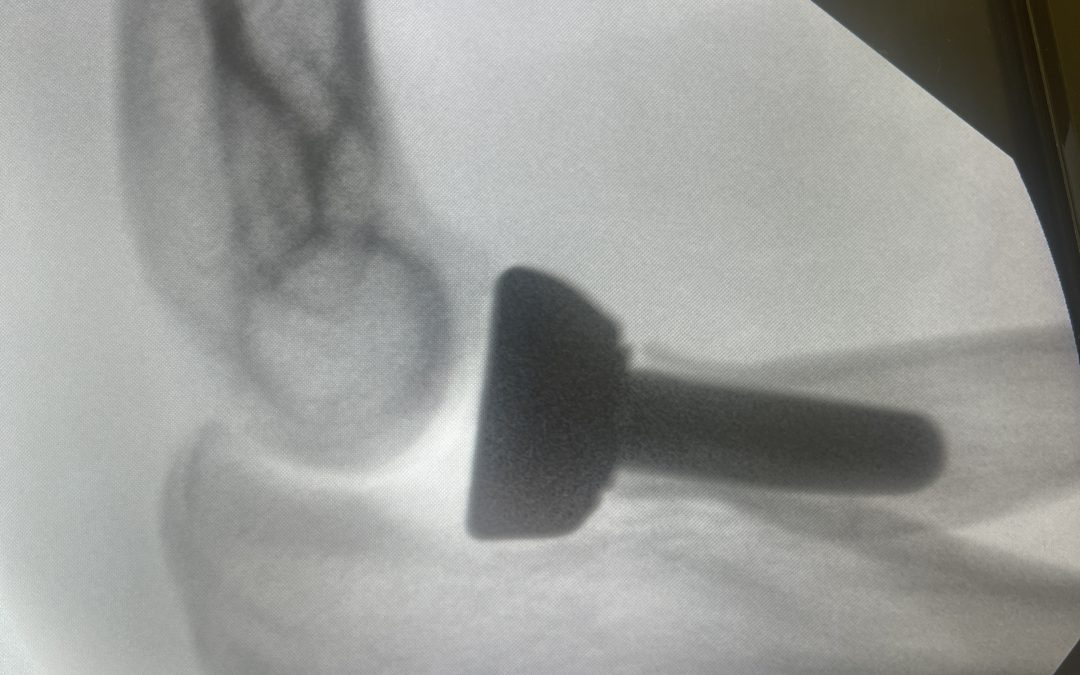

Fracturas de Cúpula Radial: Todo lo que debes saber Las fracturas de cúpula radial, también conocidas como fracturas de cabeza del radio, son lesiones frecuentes que afectan la articulación del codo. Representan aproximadamente el 30% de todas las fracturas del codo y...